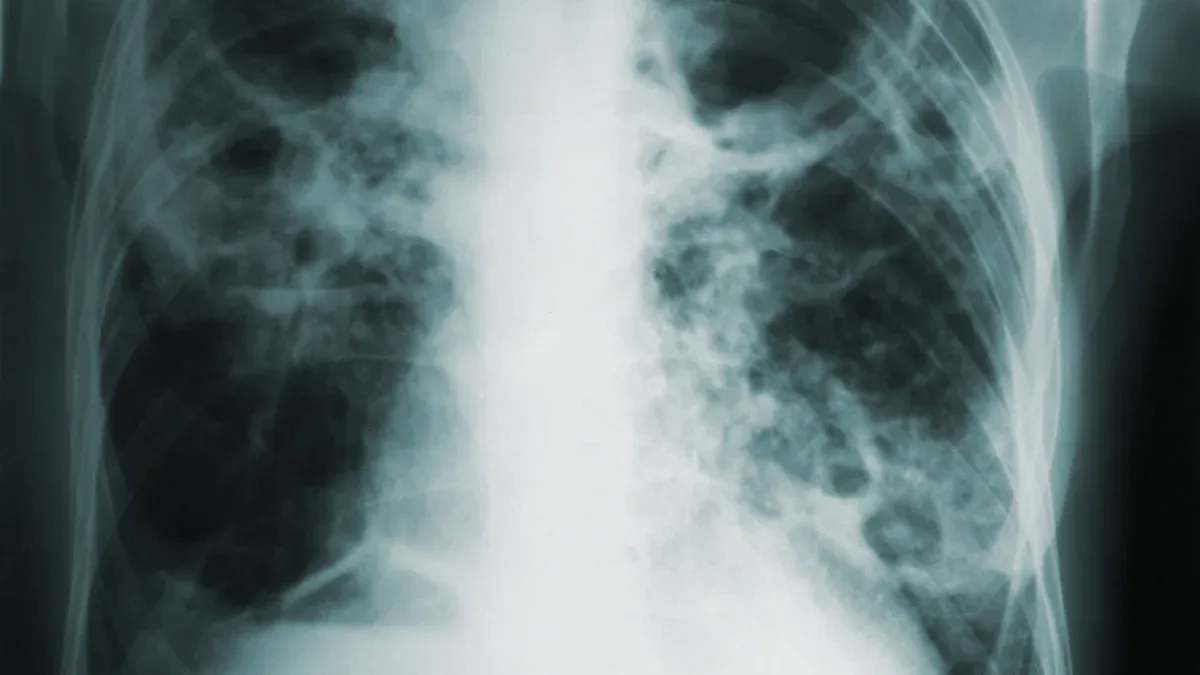

You might wonder, can you vape cbd oil without hurting your lungs? Recent reports show that people who use vaping cannabis products, including CBD oil, have developed serious lung problems. Doctors have seen more cases of lung diseases like EVALI, which stands for e-cigarette or vaping product use-associated lung injury. These cases often happen in people who use vaping cannabis oils, not just nicotine.

When you ask, can you vape cbd oil and avoid lung disease, you need to look at the facts. Vaping cannabis can cause your airways to swell and make it harder to breathe. Some people who never smoked tobacco still got sick after using vaping cannabis oils. This means the risk does not only come from tobacco.

You might wonder what happens to your lungs when you vape CBD oil. Scientists say vaping can make your lungs swell and get sore. Your body sends immune cells to help, but these cells release chemicals called cytokines. Some cytokines are IL-1β, IL-6, IL-8, and TNF-α. These chemicals make your lungs feel worse. Doctors often see special cells in the lungs of people who get hurt from vaping. These cells show your lungs are trying to fight off damage from chemicals. You may start to cough more or have trouble breathing. Studies show neutrophils, a kind of white blood cell, get very busy in your lungs. They let out proteins that make your lungs more irritated. If your vape has vitamin E acetate, your lungs can get even more hurt. Scientists found more albumin in lung fluid and more leukocytes in mice that breathed in these chemicals. This means your lungs get hurt and swollen.

Your lungs have another problem called oxidative stress when you breathe in CBD aerosols. This happens when bad molecules build up and hurt your lung cells. Scientists found that markers like myeloperoxidase and neutrophil elastase go up after vaping. These markers show your lungs are under attack and trying to heal. The lining of your lungs can break down, so germs can get in and cause infections. CBD aerosols can make the barrier in your lungs weaker. This makes your lungs more likely to get swollen. Over time, your lungs may not work as well, and you could get long-term problems.

You might notice breathing changes soon after vaping CBD oil. Many people say they cough, feel chest pain, or have trouble breathing. Doctors have seen cases of pneumonia and bronchiolitis from vaping. These problems can quickly make your lungs less healthy. Your airways may feel tight or sore. Some people get swelling and stress in their lungs right away.

If you keep vaping CBD oil, you may get lasting health problems. Breathing in vapor for a long time can hurt your lungs. You could get diseases like COPD or emphysema. Your lungs may get scars, making it hard to breathe. Studies show long-term use can damage cells and raise cancer risk. Swelling that does not go away can make your lungs more likely to get cancer.